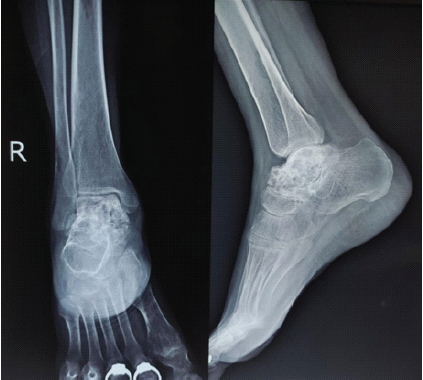

On follow-up, fluid from the lesion was aspirated under image guidance, and polidocanol injection was administered percutaneously at a dose of 3 mL/kg. The patient was advised full weight bearing along with oral analgesics and antibiotics. The patient showed improvement in pain and a decrease in the size of swelling 1 month later (Fig. 5). The polidocanol injection was repeated twice after a period of 6 months. After 2 years of follow-up, the patient had resolution of the swelling and minimal pain (Fig. 6).

Figure 5: 2-month follow-up radiograph of the right foot of the patient in anteroposterior and lateral view, showing sclerosis of the talus.